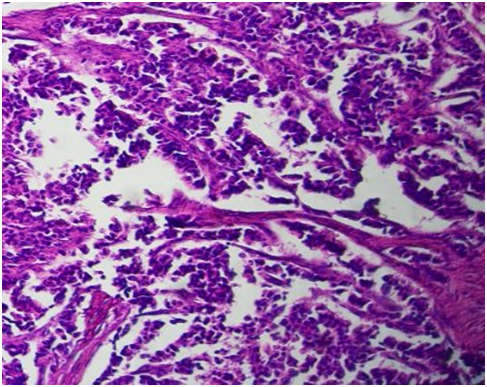

A 51-year-old woman, clinically asymptomatic who hospitalized following the discovery by a systematic radiography of a nodule of the right apical lobe. The clinical examination was normal. A thoracic computed tomography (CT) scans was performed which confirmed the presence of a small nodule of 12x16mm (Figure 1). Bronchic fibroscopy showed a diffuse inflammatory of the bronchial tree without a tumoral bud. A scannoguided biopsy was performed. The microscopic study revealed a pulmonary parenchyma whose bronchial cells are replaced by neuroendocrine cells carrying appareance of diffuse idiopathic hyperplasia of the neuroendocrine cells (Figure 2), associated with a tumor proliferation made of small nests (Figure 3) of cells with a eosinophilic cytoplasm, and a homogeneous nuclei with a molted chromatin, without mitoses (Figure 4). The stroma is vascular endocrinoid. The immunohistochemical complement showed a positivity of the tumor cells described to synaptophysin (Figure 5) and to chromogranin (Figure 6). The final diagnosis is diffuse idiopathic pulmonary neuroendocrine cells hyperplasia (DIPNECH), associated with a typical carcinoid tumor. The patient was benefecied of resection of this nodule. Three years after the operation, the patient is still alive and no tumor recurrence has been detected so far.

Figure 2 Pulmonary parenchyma whose bronchial cells are replaced by neuroendocrine cells carrying out aspects of diffuse idiopathic hyperplasia of neuroendocrine cells (HEx200).

Figure 3 Neuroendocrine tumor proliferation made of small nests (HEx100).